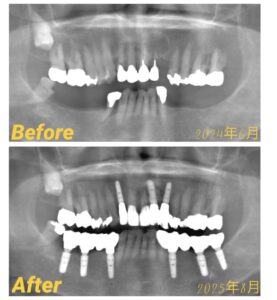

今回は、フルマウス症例のご紹介です。

レントゲン写真

こちらの患者様(70代女性)は初診時は、

下の奥歯は両側とも、ほとんど歯がない状態でした。

また、上の歯にも欠損や治療が必要な部分があり、

お口全体で噛むことが難しい状況でした。

残せる歯はできるだけ保存し、欠損している部分にはインプラント治療を行いました。

銀歯だったところは、外して中をきれいに整えたうえで、

フルジルコニアの被せ物を入れています。

同時に、歯周病治療やクリーニングを進め、歯ぐきの状態も整えています。

最終的には、お口全体でしっかり噛める状態を目指した治療です。

治療期間:2024年6月~2025年8月

担当医:齋藤理事長